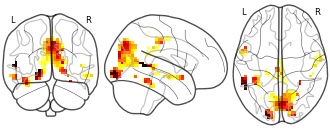

Atlases of cognition with large-scale human brain mapping: visual words

EmailClick to copy linkLink copied Cite(2018). Atlases of cognition with large-scale human brain mapping: visual words [Dataset]. http://identifiers.org/neurovault.image:109683niftiAvailable download formatsUnique identifierhttps://identifiers.org/neurovault.image:109683Dataset updatedDec 3, 2018License

Cite(2018). Atlases of cognition with large-scale human brain mapping: visual words [Dataset]. http://identifiers.org/neurovault.image:109683niftiAvailable download formatsUnique identifierhttps://identifiers.org/neurovault.image:109683Dataset updatedDec 3, 2018LicenseCC0 1.0 Universal Public Domain Dedicationhttps://creativecommons.org/publicdomain/zero/1.0/

License information was derived automaticallyDescriptionvisual_words.nii.gz

Collection description

Atlases of various aspects of cognition estimated via large-scale decoding across many studies

Subject species

homo sapiens

Map type

Other